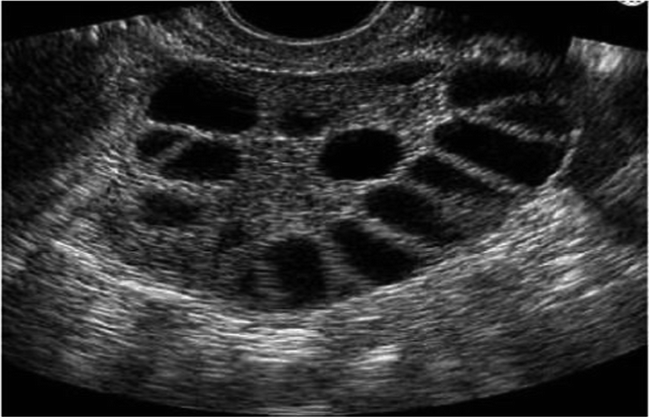

PCOS on Ultrasound

Below are transvaginal ultrasound images of the ovaries. The dark areas are what are called follicles, and each follicle is fluid-filled. If a patient has 12 or more of these follicles in their ovaries, your doctor may consider further testing for PCOS.